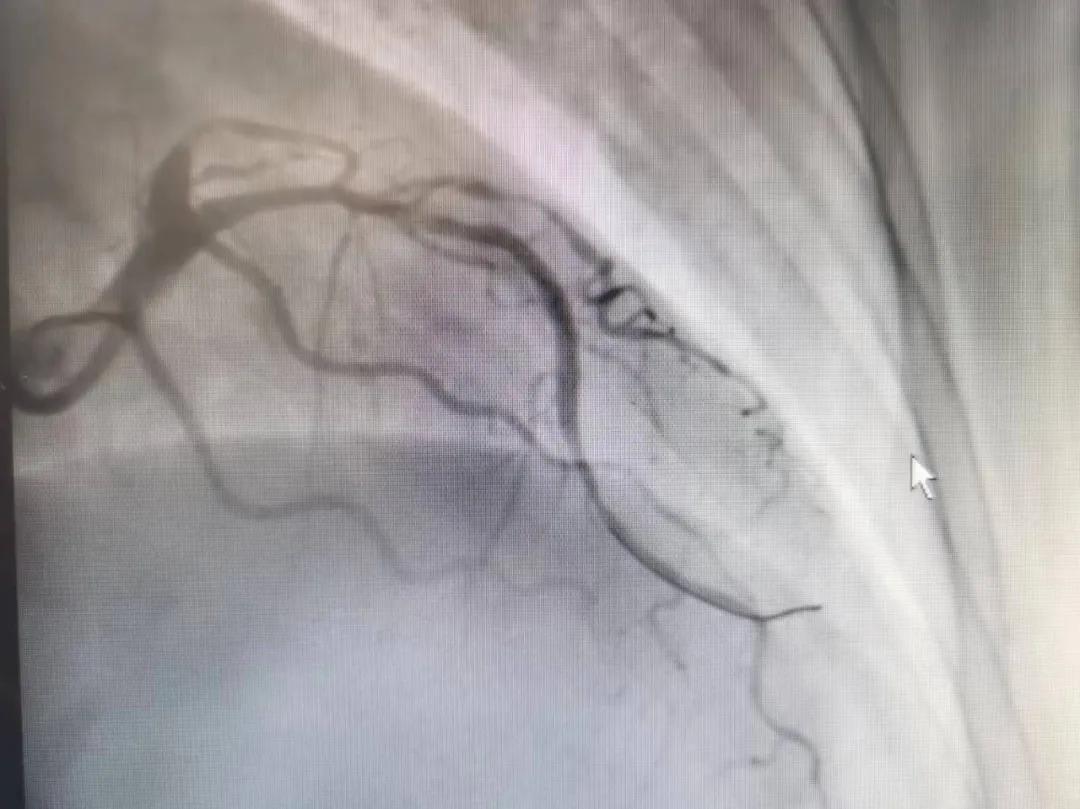

病人是位六十多歲的女性患者,有長(zhǎng)期高血壓病史,1個(gè)月前開(kāi)始出現(xiàn)胸悶胸痛,口服藥物治療效果不佳,經(jīng)朋友介紹,來(lái)到市二院心血管內(nèi)科。入院后完善冠狀動(dòng)脈造影提示:前降支全程彌漫性狹窄伴鈣化,最重95%,回旋支狹窄約85%,右冠脈全程狹窄伴鈣化,最重60%。血管內(nèi)超聲顯示右冠脈開(kāi)口面積3.36mm²,可見(jiàn)環(huán)形鈣化,考慮患者病變程度重、鈣化明顯,常規(guī)器械無(wú)法實(shí)現(xiàn)病變的良好預(yù)處理,且有很高的冠脈穿孔、血管夾層的風(fēng)險(xiǎn)。

術(shù)前

王瑾院長(zhǎng)和李慧新主任帶領(lǐng)介入團(tuán)隊(duì)充分評(píng)估,決定行前降支冠狀動(dòng)脈鈣化病變旋磨術(shù),術(shù)中應(yīng)用1.5mm旋磨頭,以15萬(wàn)-17萬(wàn)轉(zhuǎn)/分速度共對(duì)病變旋磨3次,累計(jì)旋磨時(shí)間60秒,后復(fù)查造影示鈣化明顯減輕,為后續(xù)操作創(chuàng)造了良好條件,隨后應(yīng)用預(yù)擴(kuò)張球囊、切割球囊再次處理病變,并順利植入支架1枚,復(fù)查造影顯示支架膨脹及貼壁良好,無(wú)夾層、血腫、慢血流等情況,手術(shù)順利完成。患者術(shù)后無(wú)不適,胸悶、胸痛癥狀明顯緩解,順利出院。